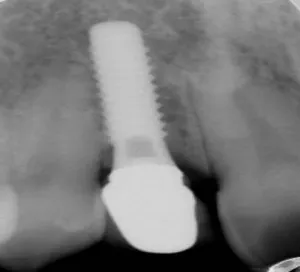

Antes: paciente con dos dientes frontales ausentes. 17 años después de colocación de implantes con injerto de encía